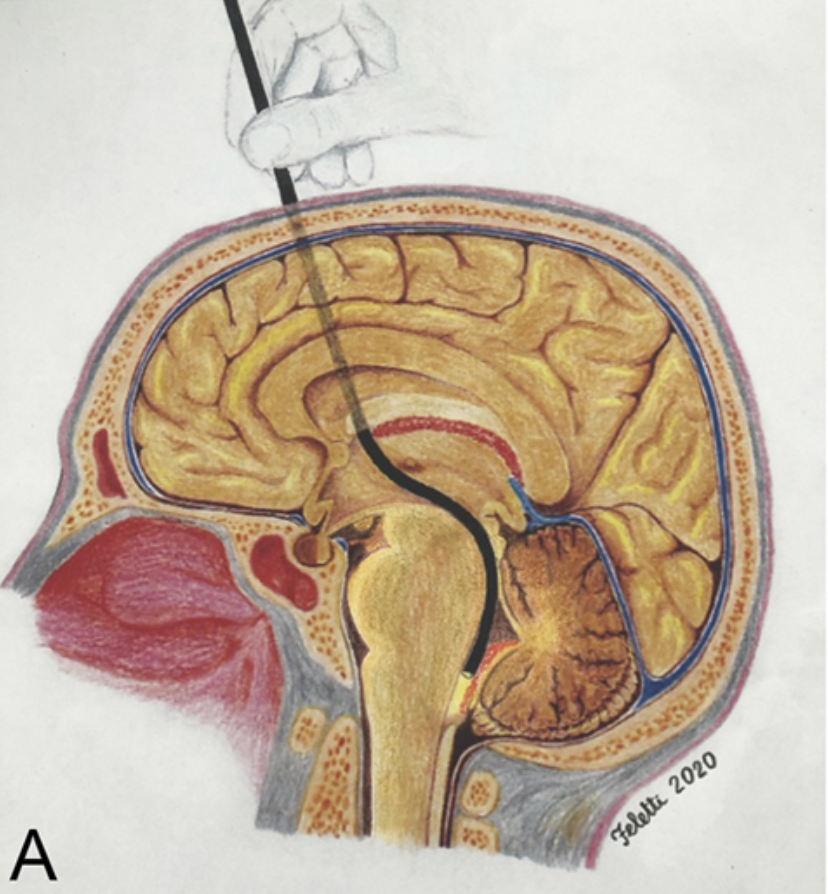

Neurochirurgo presso l'Azienda Ospedaliero-Universitaria Integrata di Verona, ha eseguito circa 3.000 interventi neurochirurgici, di cui oltre 2.000 come primo operatore. Affianca all'attività clinica un impegno costante nella ricerca e nella didattica universitaria. È autore di oltre 100 pubblicazioni peer-reviewed e 10 capitoli di libro, illustratore anatomico per pubblicazioni scientifiche ed Associate Editor di Frontiers in Surgery — Neurosurgery. Ha maturato esperienze di ricerca e cliniche all'estero, tra cui l'Università della California a San Francisco (UCSF), la Fujita Health University (Nagoya) e la Fudan University (Shanghai).

I suoi interessi chirurgici principali comprendono la chirurgia vertebrale, la chirurgia cerebrovascolare, i tumori cerebrali, i tumori intramidollari, la neuroendoscopia e la neurochirurgia funzionale. È inoltre titolare di un brevetto per un elettrodo di neuromonitoraggio in ambito endoscopico (brevetto italiano ed europeo).